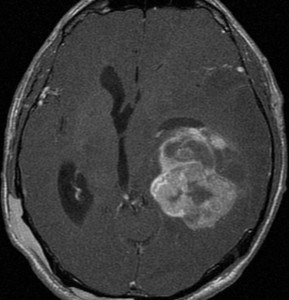

思春期に難治性てんかんで発症した典型例 occult PXA?

7歳児に頭痛に嘔気を伴う,1分間くらいの短い発作で発症しました。

左は8歳時のMRIで,異常所見がありませんでした。左側頭葉に発作時の異常脳波所見が認められ,側頭葉てんかんの診断でカルバマゼピンの投与が開始されました。9歳時に精神症状を呈する発作となりレベチラセタムとゾニザミドが加えられました。右側のMRIは9歳時のものですが異常所見はありませんでした。前後にさまざまな画像が撮影されていましたが脳腫瘍の所見はありませんでした。

11歳時のMRIで側頭葉下面に異常所見が出現しました。

カルバマゼピン,ガバペンチン,ゾニザミド,ラコサミド,クロバザムの5剤投与を受けていましたが発作は制御できませんでした。

12歳時,私のところへ来た時のガドリニウム増強像です。開頭手術で扁桃体を含めて全摘出してから発作は止まり,術後3年で抗てんかん薬は中断できています。